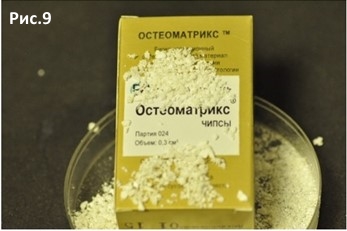

Вскрываем Остеоматрикс чипсы Объём 0,5 см/куб. Рис.9

Остеоматрикс чипсы Объём 0,5 см/куб. = 1540р.